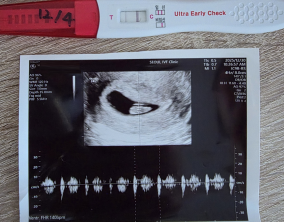

심장소리 이후, 함께 웃게 된 임밍아웃

유정원장님 치료 과정 내내 항상 따뜻하게 진료해 주셔서 감사한 마음이 큽니다. 덕분에 불안한 순간에도 마음을 다잡고 치료를 이어갈 수 있었습니다.